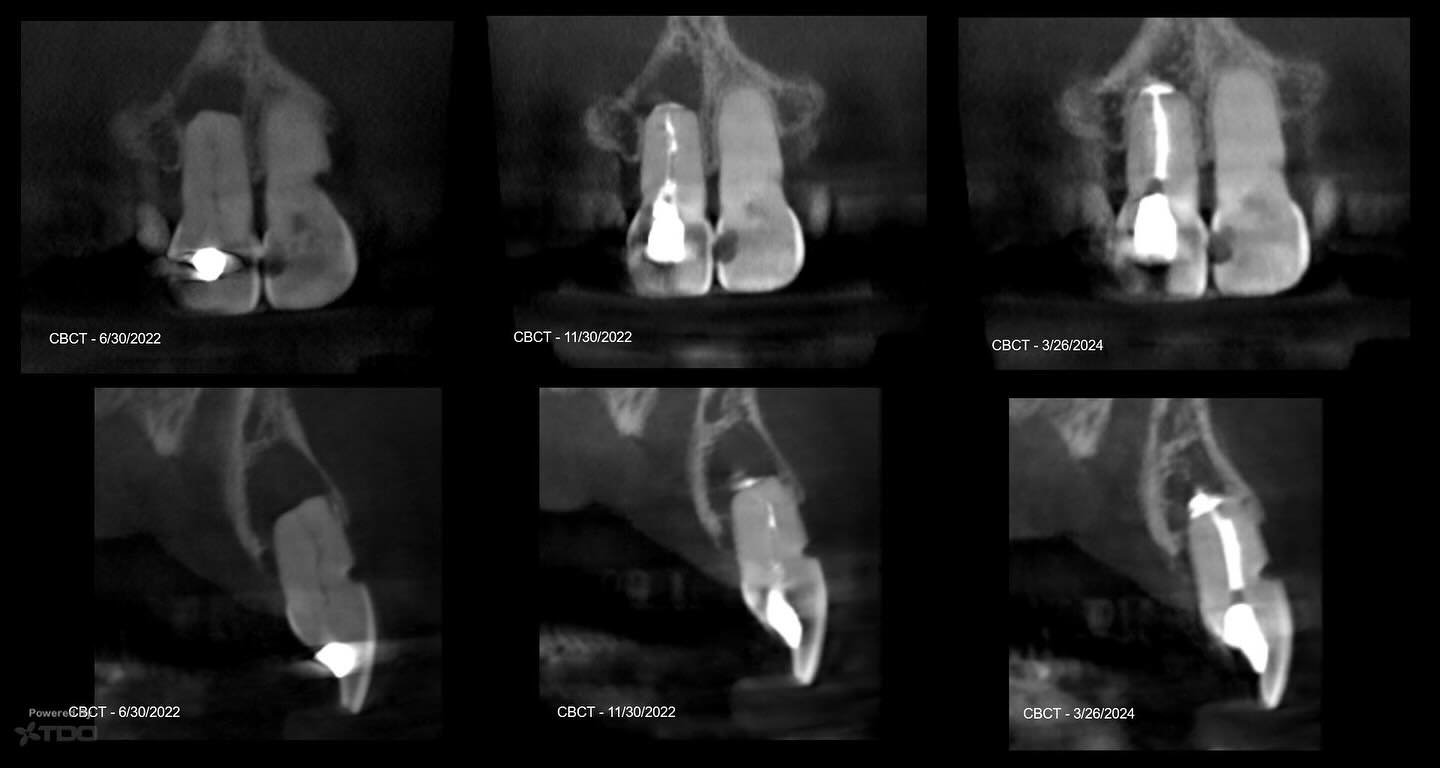

I am a board-certified endodontist with advanced specialty training and an academic interest in diagnostic reasoning, retreatment, and microsurgical endodontics. My work emphasizes CBCT-guided decision-making, interdisciplinary collaboration, and evidence-based care in complex clinical scenarios.